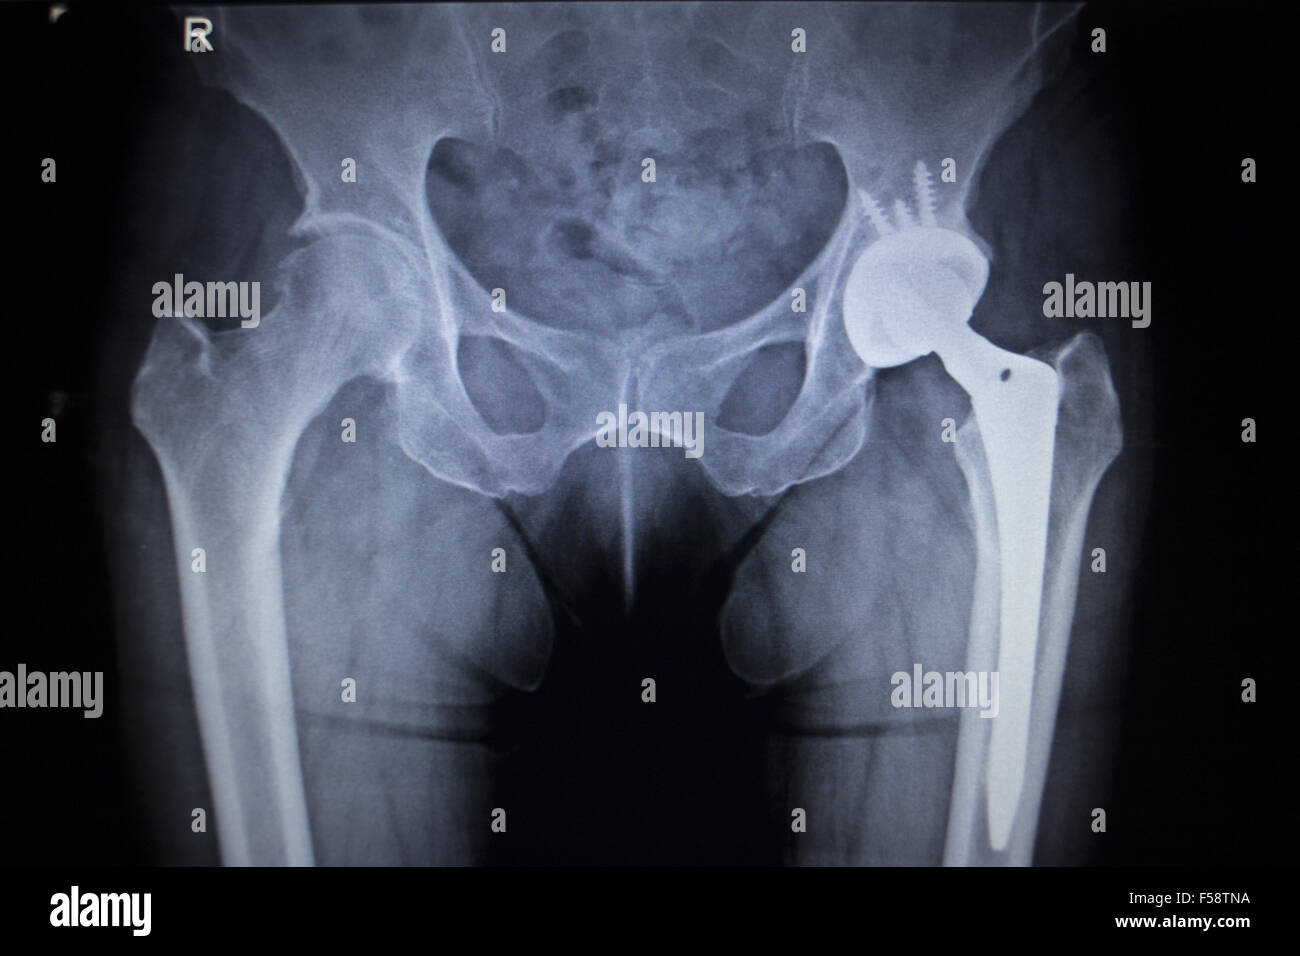

Xray scan image of hip joints with orthopedic hip joint replacement Sc Joint X Rays An articular fibrocartilaginous disc divides the joint into two separate synovial spaces. The anterior oblique projections of the sternoclavicular joints are complimentary to the front on pa view in the sternoclavicular joint. The joint is supported by a thick capsule reinforced by the anterior (green) and posterior sternoclavicular ligaments. Schematic drawing of an anterior view of the sclj. Sternoclavicular joint. Sc Joint X Rays.